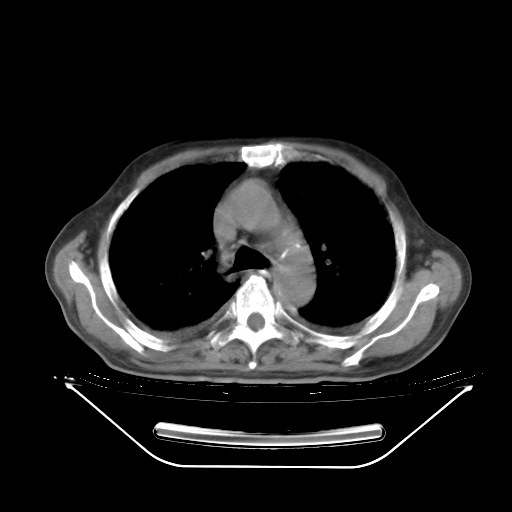

今天复查肺部CT,发现双肺广泛磨玻璃样改变。所以我把3月19日和5月9日相隔50天的肺部CT上传。请大家会诊。

5月9日肺部CT(在4月27日齐鲁医院肺部CT描述部分肺组织磨玻璃样改变,12天后肺组织广泛磨玻璃样改变)

大致读了系列胸部CT:纵隔窗无明显异常,肺窗:从4、27至今:主要是双肺中下野外带可见毛玻璃样改变,目前处于急性肺泡炎阶段,至于原因考虑1、结替组织或胶原血管性疾病所致?2、恶性疾病如恶组在肺部所致的表现或细支气管肺泡癌?3、药物或其它原因如肺蛋白沉着症所致肺泡炎目前不太可能?总之,明天就去请我院的呼吸科、感染科、血液科和临免专家会诊哈。